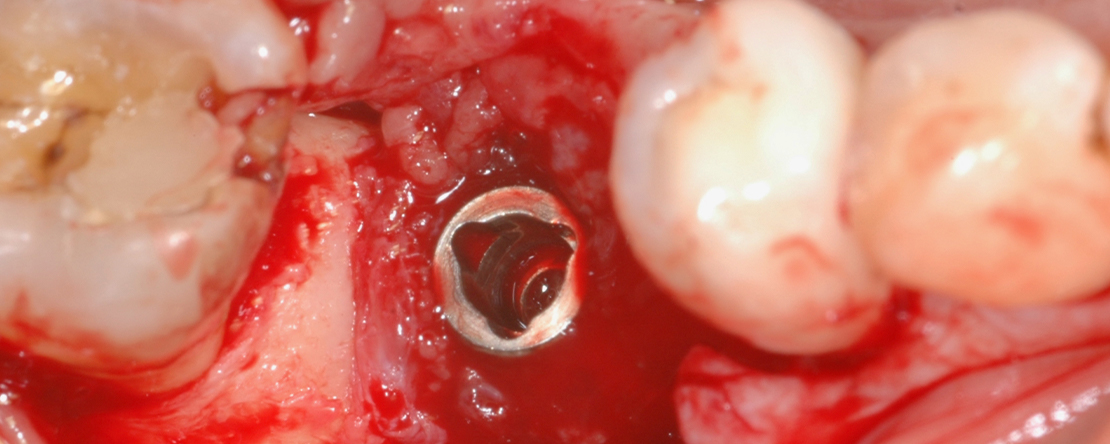

Os insucessos em implantes dentários podem ocorrer por diversos motivos e exigem estratégias específicas de tratamento conforme a sua causa e gravidade. A deteção precoce e a intervenção rápida são fundamentais para evitar complicações adicionais, como infeção ou perda óssea.

Entre as principais causas de insucesso estão: ausência de osteointegração, peri-implantite, falhas mecânicas, complicações protéticas, erros cirúrgicos ou falta de planeamento pré-cirúrgico.

As opções de tratamento incluem a remoção e substituição do implante, com possível enxerto ósseo ou regeneração óssea guiada; enxertos ósseos e procedimentos de regeneração para restaurar o volume ósseo; tratamento da peri-implantite com descontaminação mecânica, terapias antimicrobianas e, se necessário, procedimentos reconstrutivos com enxertos ósseos; além da reparação ou substituição dos componentes protéticos danificados.